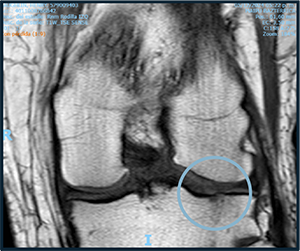

Before starting cell therapy, patients undergo a magnetic resonance imaging (MRI) or computed tomography (CT) scan to assess the condition of the bone and soft tissues of the knee.